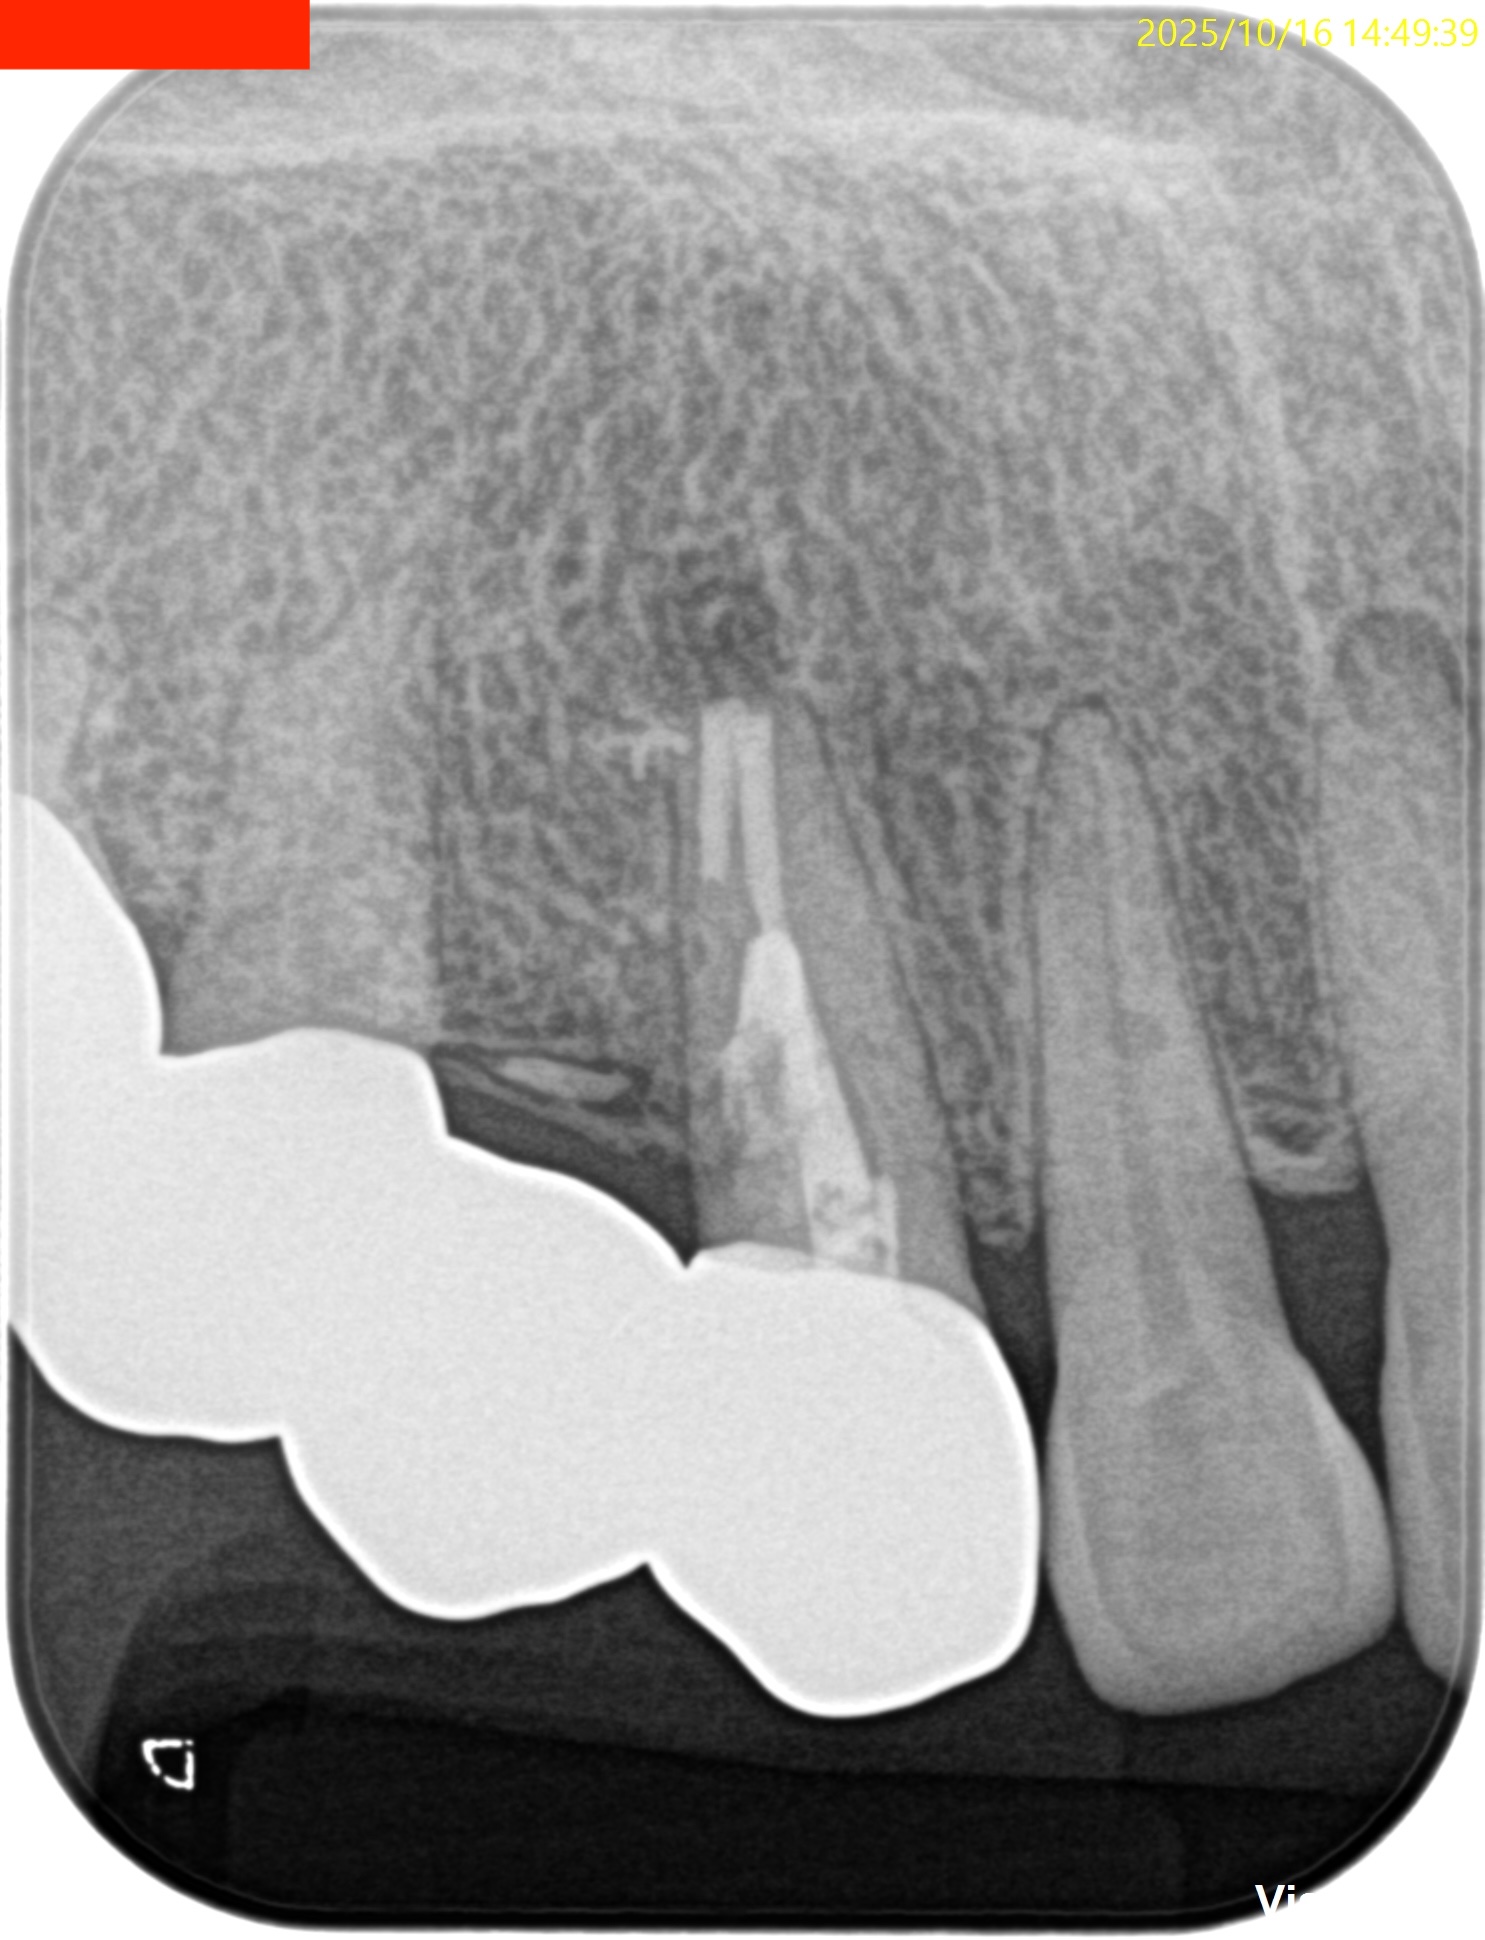

PA, CBCTを撮影した。

しょっぱい逆根管形成になったが主根管は確保されたので縫合して終了した。